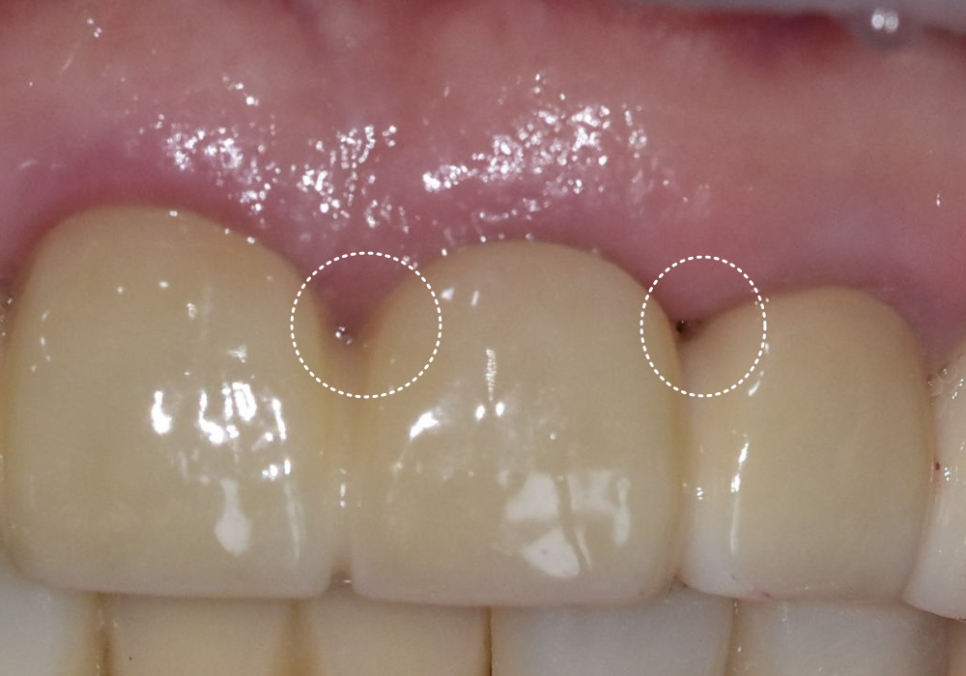

치료가 마무리된 후의 모습입니다.

검게 변색되었던 부분들이 사라지고

인상이 전체적으로 깨끗하고 단정해 보이네요.^^

240223(전) 240711(후)